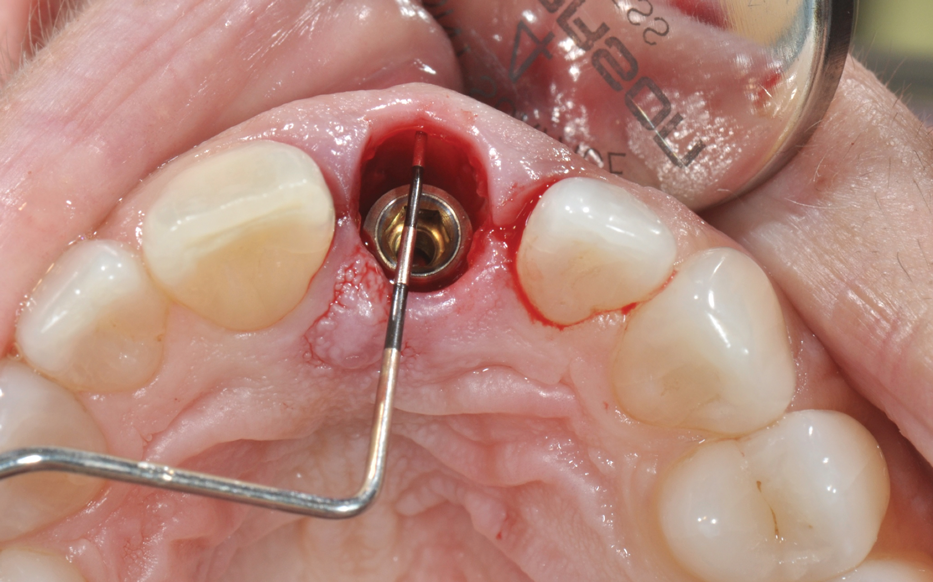

In the molar region, the preparation of sites with large septa presents its own challenges, especially when carried out in an analog fashion. Fully guided preparation of the osteotomy and implant placement reduces the potential for the drill to drift or the implant to migrate into the adjacent socket defects (Figure 5 through Figure 9).

(7.) Restoratively centered guided osteotomy and implant insertion.

Figure 7

(8.) Restoratively centered guided osteotomy and implant insertion.

Figure 8